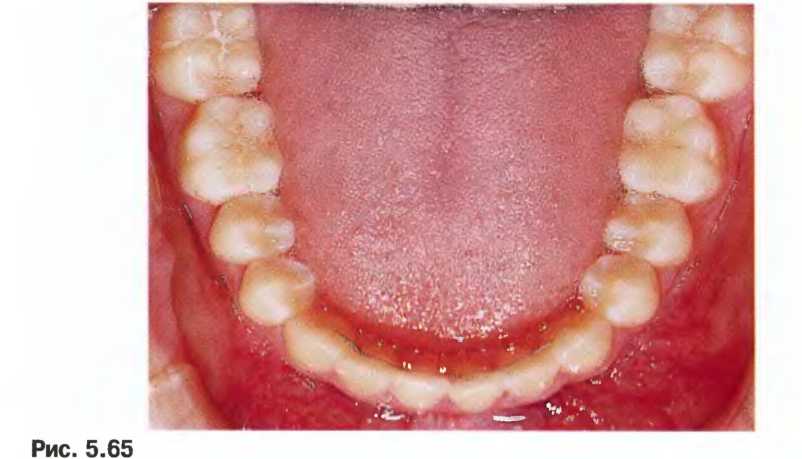

Вид с окклюзионной стороны в начале лечения - язычная дуга на нижнем ряду и нёбная дуга на верхнем ряду с восьмиобразными связками для обеспечения контроля и последующей ретракции клыков.